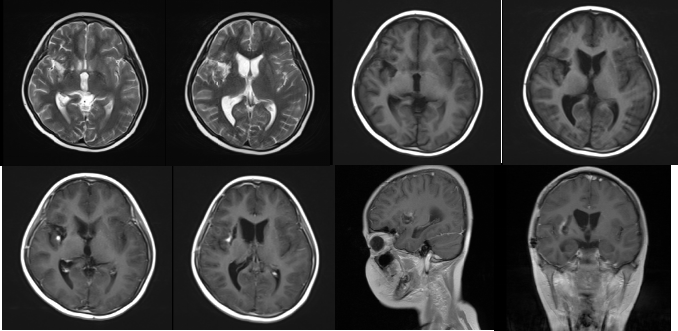

术前增强MRI

术后增强MRI

化疗前复查头颅增强MRI(术后2周)

2周期化疗后复查头颅增强MRI